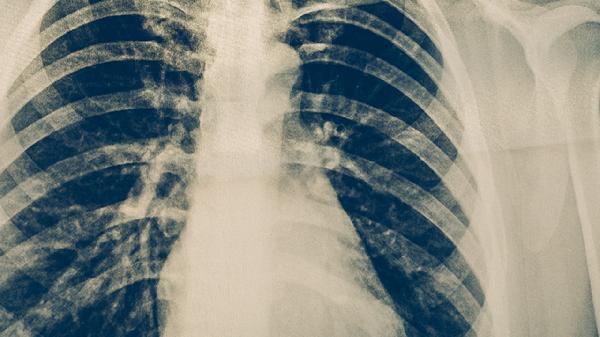

轻度肺炎一般可以通过药物治疗痊愈。轻度肺炎的治疗主要有阿莫西林胶囊、头孢克肟分散片、盐酸左氧氟沙星片、阿奇霉素片、氨溴索口服溶液等药物,建议及时就医,在医生指导下用药。